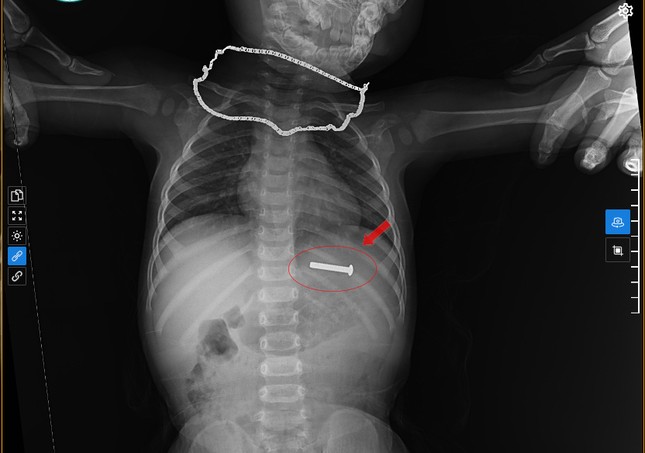

26/02/2025 16:17Đinh vít sắt dài 5cm trong dạ dày bé trai 15 tháng tuổi

Ngày 6/2, Bệnh viện đa khoa Minh An (huyện Quỳnh Lưu, Nghệ An ) cho biết, đơn vị này vừa thực hiện ca nội soi gắp thành công dị vật là đinh vít sắt trong dạ dày một bé trai 15 tháng tuổi trú tại xã An Hòa (huyện Quỳnh Lưu).

Theo lời kể của gia đình, chiều 5/2, cháu bé cầm 2 đinh vít sắt chơi đùa. Ít phút sau, gia đình phát hiện trên tay cháu bé chỉ còn 1 đinh vít sắt. Nghi ngờ bé đã nuốt chiếc đinh vít sắt nên người thân lập tức đưa đến Bệnh viện đa khoa Minh An để thăm khám.

Tại bệnh viện, các bác sĩ đã tiến hành chụp X-quang, siêu âm và xác định đinh vít sắt đang nằm trong dạ dày của cháu bé nên tiến hành thủ thuật nội soi gắp dị vật . Sau 15 phút thực hiện, ekip nội soi đã gắp thành công chiếc đinh vít sắt ra ngoài an toàn.

“Quá trình gắp dị vật cho bệnh nhi khá khó khăn vì dị vật trơn, tròn kèm bã thức ăn trước đó nên rất khó gắp. Tuy nhiên, rất may mắn khi bệnh nhi được phát hiện và xử lý sớm. Nếu không xử lý, dị vật có thể xuống ruột gây nhiều biến chứng nguy hiểm như thủng ruột, chảy máu… lúc đó chắc chắn phải phẫu thuật mở”, Bác sĩ Nguyễn Đình Lan - người trực tiếp thực hiện nội soi gắp dị vật nói.

Các bác sĩ khuyến cáo, gia đình có trẻ nhỏ cần theo dõi sát sao và tránh không cho trẻ chơi với các vật sắc nhọn như đinh, vít, đồng xu…. Nếu phát hiện trẻ nuốt dị vật cần khẩn trương đưa đến cơ sở y tế uy tín, đầy đủ trang thiết bị để thăm khám và điều trị kịp thời.